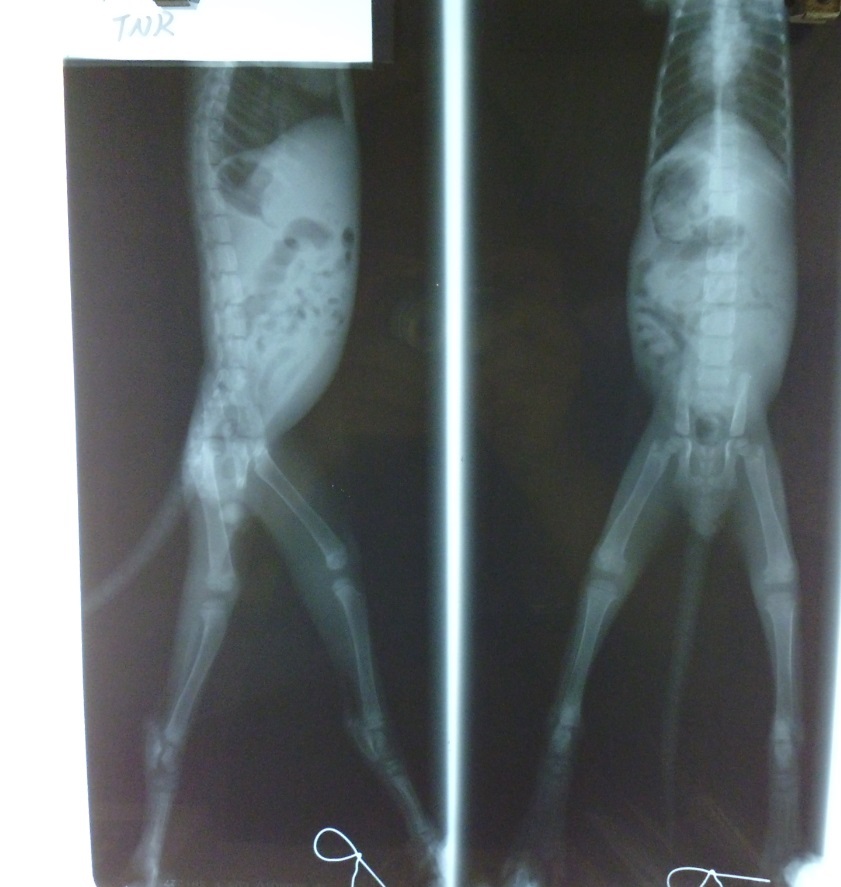

- 編號: 2873

主題: 被人蓄意丟棄公廁的幼貓 申請者姓名: 拳四郎 花色: 申請日期: 2013-08-19 04:56:50 申請者部落格: 申請者臉書網址: 所在縣市/合作醫院: 高雄市/新德民動物醫院 治療費用: 10840元 需求人數: 12人 已結案 (2013-09-03 16:24:04) 報名人員: 00(已付款)、布蘭卡小姐(已付款)、Alumi Lu(已付款)、Candice Chao(已付款)、Kim Meng(已付款)、Emily Tseng x2(已付款)、sally x3(已付款)、philip(已付款)、limit(已付款)、 候補人員: 動物病情說明: 7月20號發現有貓貓被丟棄公廁內

重點是小貓的下半身都沒有反應

不知是否為高處摔落!

還是人為造成!

7月20-25號住院在保溫箱治療

是危險期!

7月26號轉一般病房-

因拉肚子及泌尿道出現腫脹

住院治療

8月13號出院

貓貓目前每3天

都要去高雄市富恩動物醫院接受治療動物近況說明: 貓貓目前每3天

都要去高雄市富恩動物醫院接受治療

內容是針灸跟紅外線